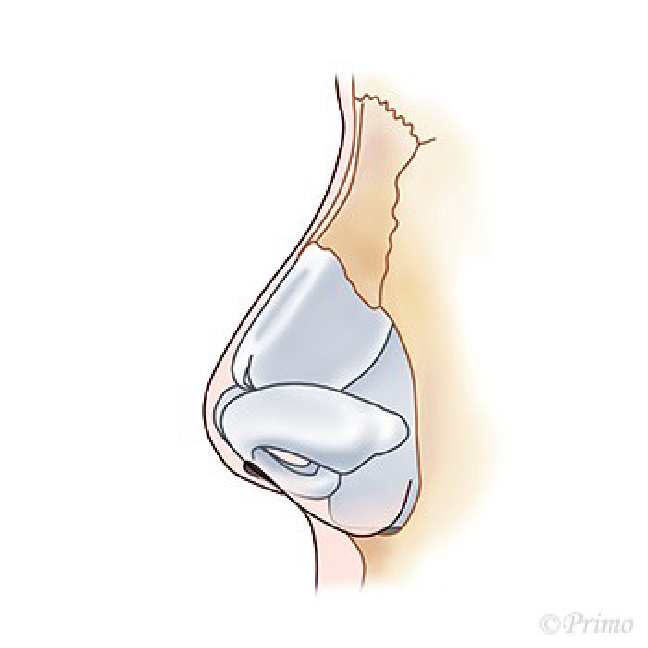

求める変化の大きさ、もともとの鼻の状態に応じ、採取部位を耳介軟骨、肋軟骨、あるいは鼻中隔軟骨から選択し、必要量のみ採取いたします。(上の図は耳介軟骨を採取して鼻中隔延長をするイメージ)

耳介軟骨からとる場合は、耳の後ろのしわに沿って約2cm程の傷から採取します。傷はほとんどわからなくなり、耳の変形も、機能障害もきたしません。

肋軟骨からとる場合は、バストのアンダーの位置に約3cm程の傷から採取します。傷は最小限になるよう形成外科縫合を行います。移植材料となる軟骨が大きくとれるので、大きな変化を求める場合や、術後の修正例の場合に適しております。採取部の変形などはありません。

鼻中隔軟骨から採取する場合は、軟骨が小さいため、それほど大きな変化を望まない場合などになります。別の所に採取部の傷を残さない良い方法です。(下の図は鼻中隔)